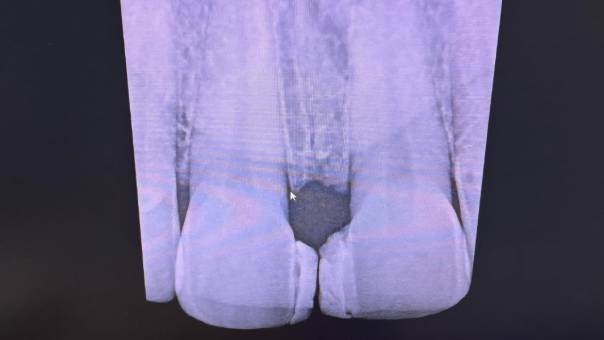

Mesioden In the IOPAR

Diagnosis: Upon clinical and radiographic examination, we discovered the presence of a mesioden—an extra tooth located between her Upper Right Central and Lateral Incisor. This supernumerary tooth was contributing to the spacing and misalignment in the anterior region.